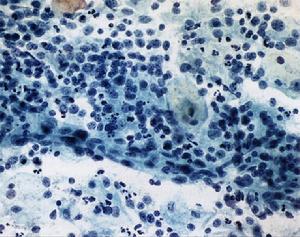

2.臨床消化內鏡檢查 可以明確消化道黏膜病變情況,估計病情直腸鏡檢查發現黏膜水腫、變脆、潰瘍並附有黏液膿性分泌物。